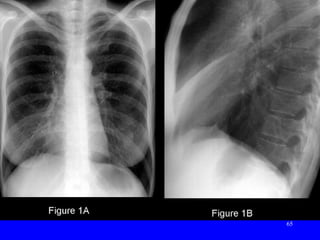

• #66ย 1A: CXR: ill-defined R perihilar opacity obscuring R heart border &amp; contains no air bronchograms. 1B: a corresponding triangular opacity with its base abutting the sternum and its apex directed toward hilum. Note anterior displacement of oblique fissure and elevation of R hemi-diaphragm. Dx: : R Middle Lobe Atelectasis